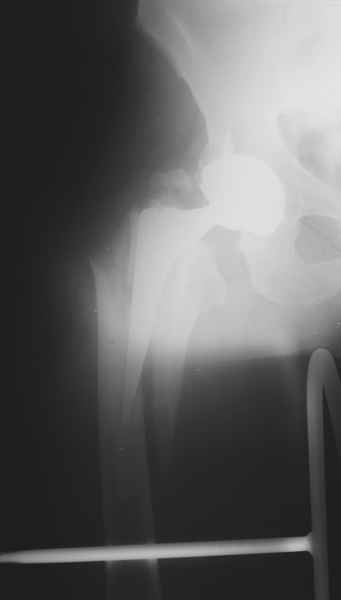

Хочется показать два подобных случая, П-ка З. 72 лет и п-т Г. 80 лет. Сразу принимаю замечание, что это были ножки цементной фиксации, просто под руками не было бесцементника.